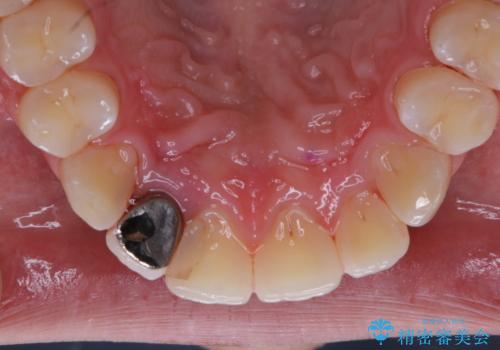

- 10年ぶりの歯科とのことで、全体の検診希望で来院されました。レントゲン撮影、歯周ポケット検査、ブラッシング指導、クリーニングを行いました。

今回はお口全体にプラーク(細菌の塊)、歯石、着色(ステイン)が付着していたため、検査後、歯科衛生士による専門的自費のPMTC(クリーニング)60分コースを行いました。

まずは、お口全体の染め出しをし、どこに汚れや磨き残しが多くついているかを明確にしました。その後、普段の歯磨きの仕方の確認や、ブラッシング指導をしました。

10年ぶりの歯科医院へ来院とのことで全体的に汚れ(バイオフィルムや着色)が多く付着してたため、自費クリーニングPMTC60分コース10000+TAXを行いました。